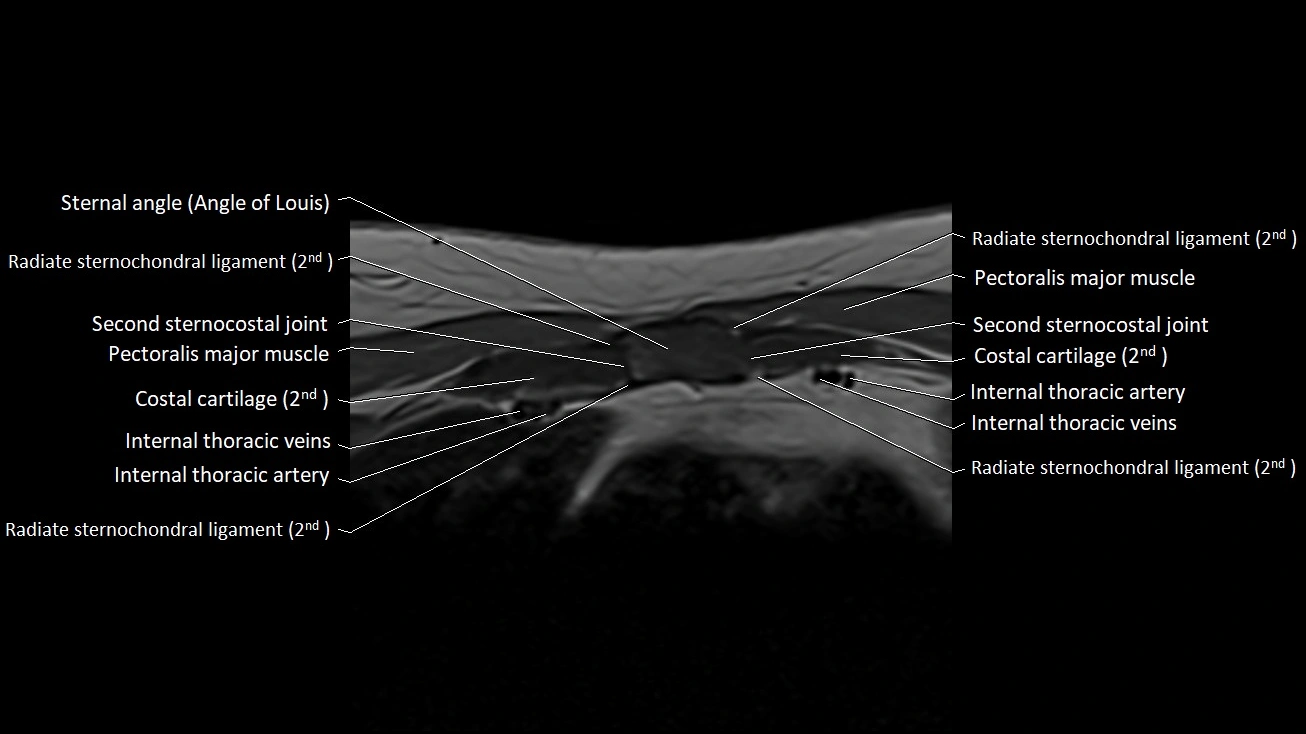

MRI images

image